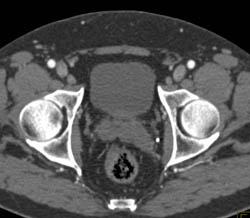

Neobladder S/P Cystectomy